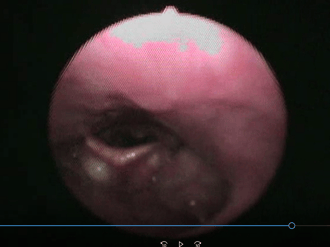

食事の経口摂取について判断に迷う場合、嚥下精密検査を行います。

当院では施設に訪問して嚥下内視鏡検査(VE)などを用いて嚥下の精密検査を行っております。

経管栄養から経口移行を安全に行うにはとても強力なツールになります。